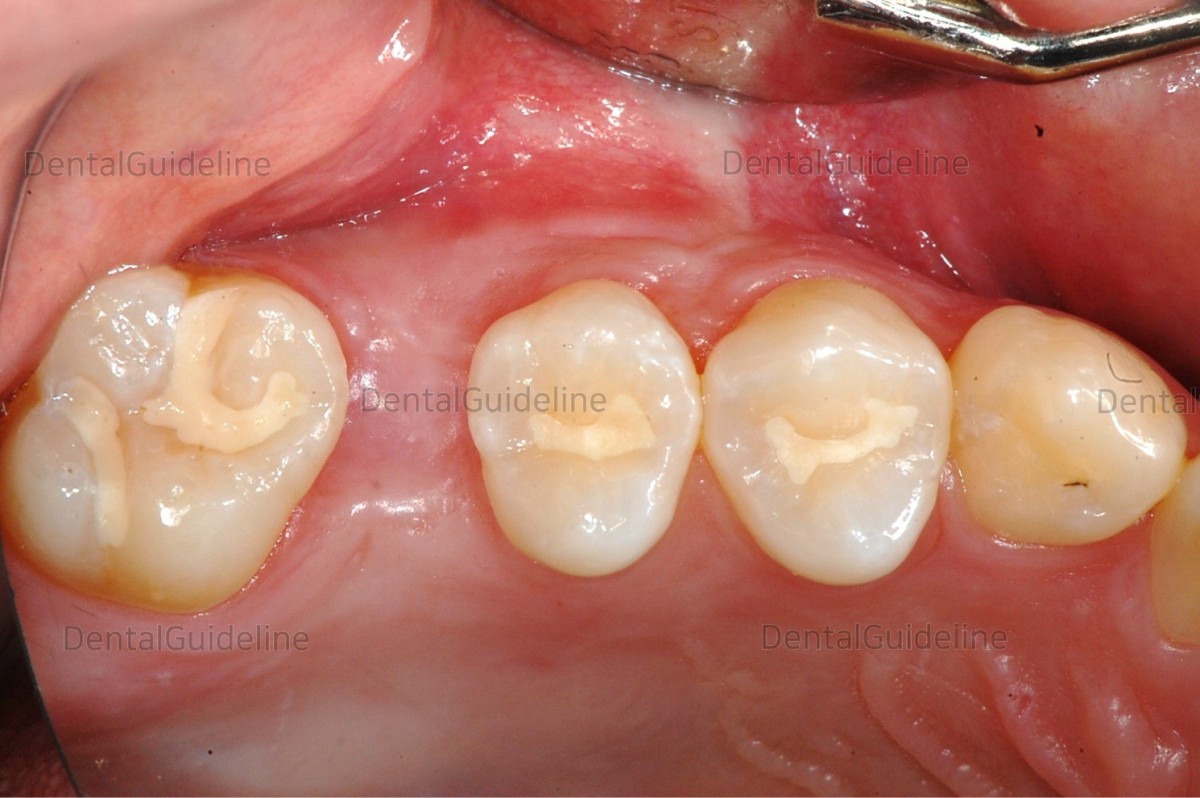

13. Photo 2 months later.![]()

14. The bracket was bonded and the segment wire was ligatured.

15. 50 days after orthodontic treatment. (coated Ni-Ti open coil spring)

![]()